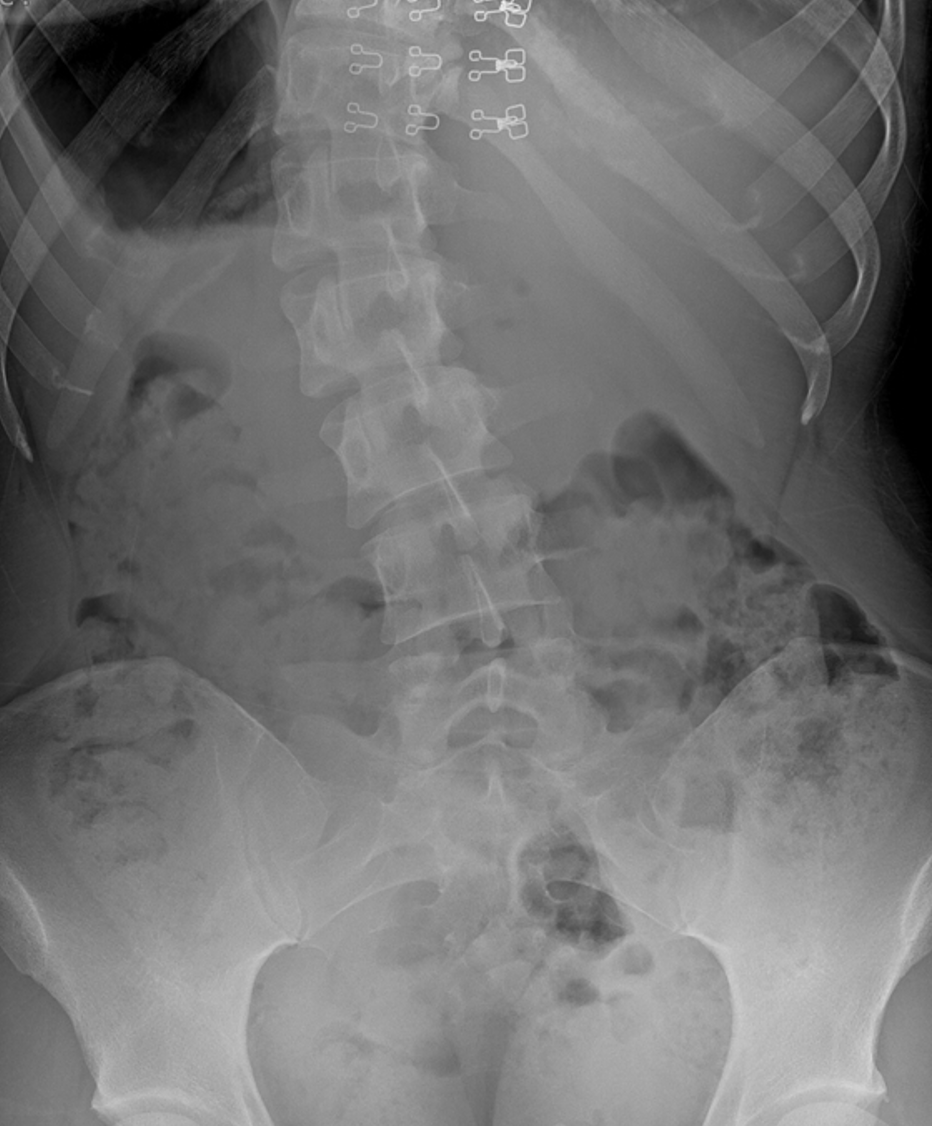

To give you some context, the image below on the left is a normal lower back x-ray – the pelvis should be aligned and the spine straight. The image on the right is my low back x-ray…

Not surprising that I was noticing some issues, right? The name for the severe curve in my lower back is called a scoliosis. The curve creates huge amounts of biomechanical changes of force and demand in my back, ribs and pelvis, and of course, can create pain.